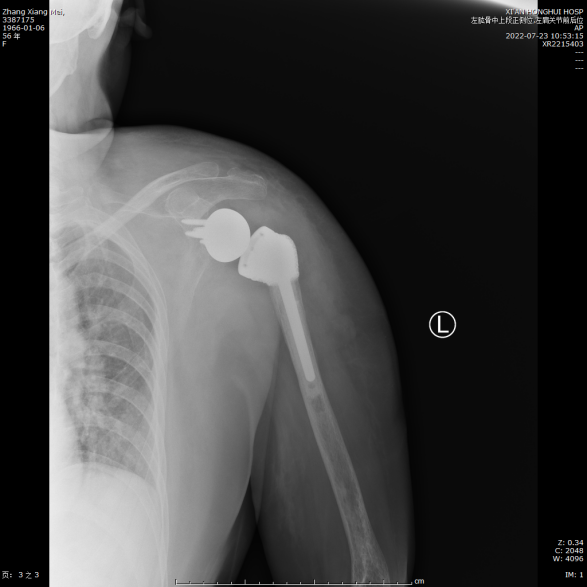

X光片显示肩关节假体在位良好

术后患者状况良好,第二天即可开始下地活动,肩关节也可以做一些简单的前后运动,X光片显示肩关节假体在位良好,目前患者已康复出院。